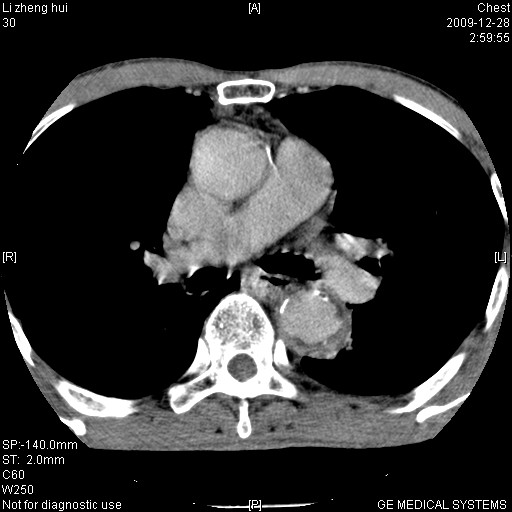

男  79岁 胸部痛急诊入院,晚上做的增强

考虑主动脉瘤?(增粗、钙化、壁血栓?)

支持,另有肝囊肿。

动脉瘤伴附壁血栓

1)考虑胸主动脉壁间血肿或夹层动脉瘤。2)多发性肝囊肿。

1)考虑胸主动脉附壁血栓或夹层动脉瘤。2)多发性肝囊肿。